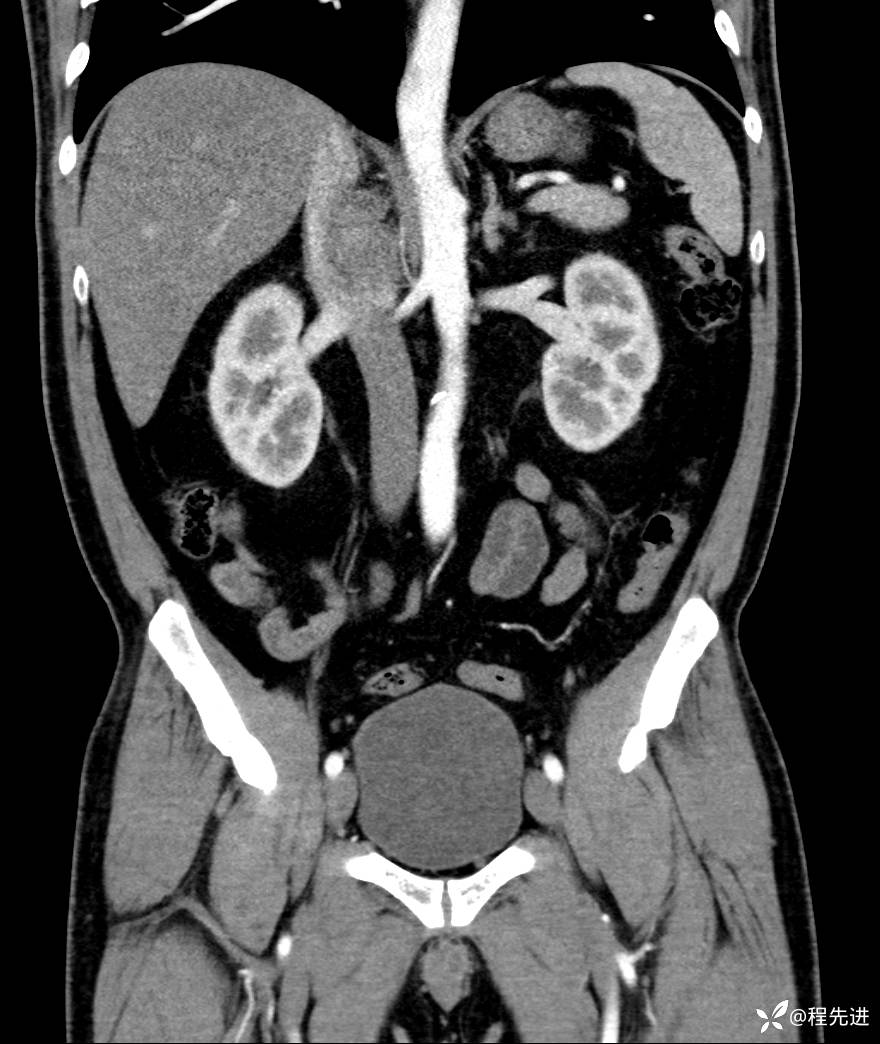

【腹盆】特别精彩病例|发现腹膜后肿物1月余

主诉:发现腹膜后肿物1月余

现病史:患者1月余前查体,行超声检查提示:后腹膜囊实性肿块;慢性胆囊炎伴胆囊内结石;无腹痛腹胀,不伴腹泻发热等;偶感腰背部酸痛。

CT平扫+增强: